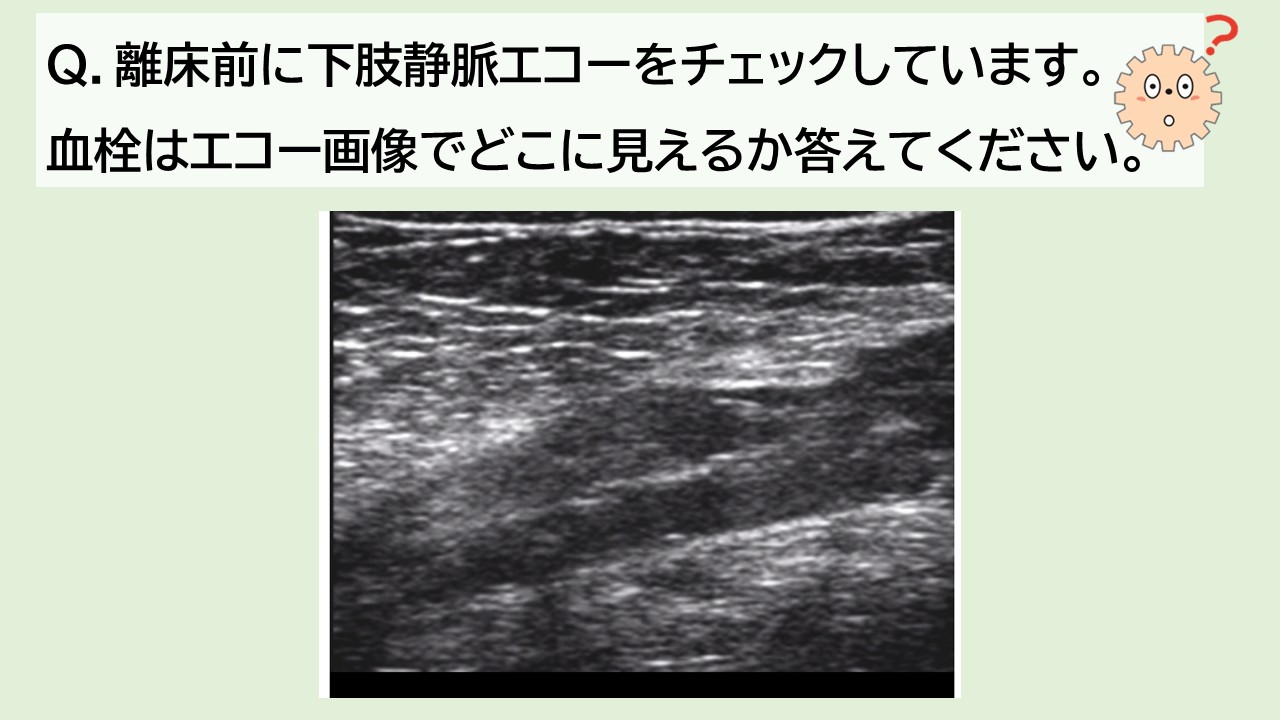

今回は、まもなく開催される新講座、超音波エコー評価とアプローチの選択 循環アセスメントとDVTに必須のエコー測定とアプローチより、問題を出題。エコーの知識の腕試しに解いてみてください。

[エコークイズの解答]

上記、循環アセスメントとDVTに必須のエコー測定とアプローチ講座では、DVT検出時の離床可否の判断についても詳しく解説します。